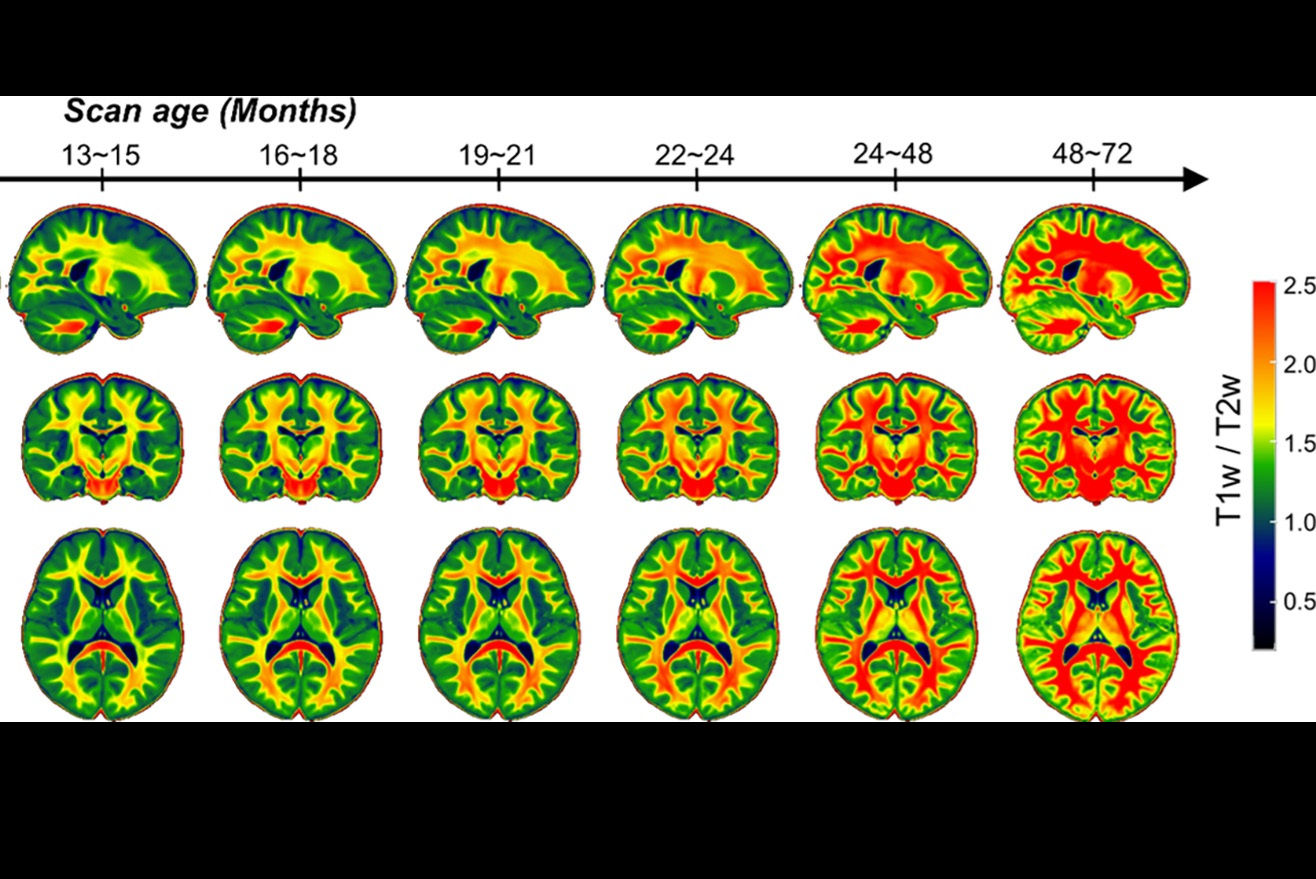

After structural brain MRI scans were performed at a term-equivalent age (mean, 40.3 weeks), the DWMA detection and segmentation algorithm was applied to the T2-weighted images. These results were also compared with visual classification of DWMA by neuroradiologists. Next, the researchers performed multivariable logistic regression analysis to assess the value of DWMA volume to predict motor development at 3 years of age.

Earlier diagnosis of motor abnormalities would facilitate targeted delivery of early interventions and novel habilitative therapies during this optimal period of brain development, according to the researchers.